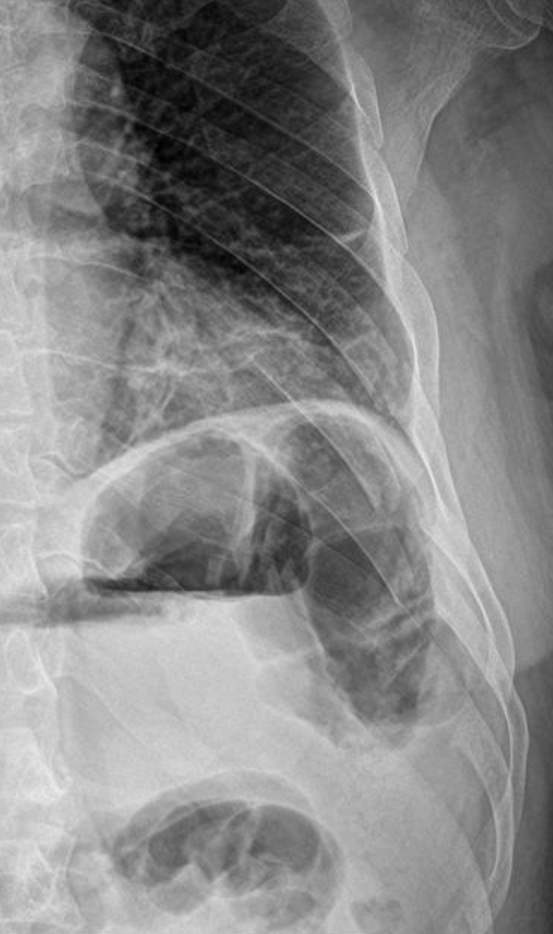

A 21-year-old female presents to the emergency room after falling from dancing on a table and injuring her right ankle. She is in severe pain and unable to bear weight comfortably with swelling and tenderness along the lateral malleolus. X-rays are taken and shown above.